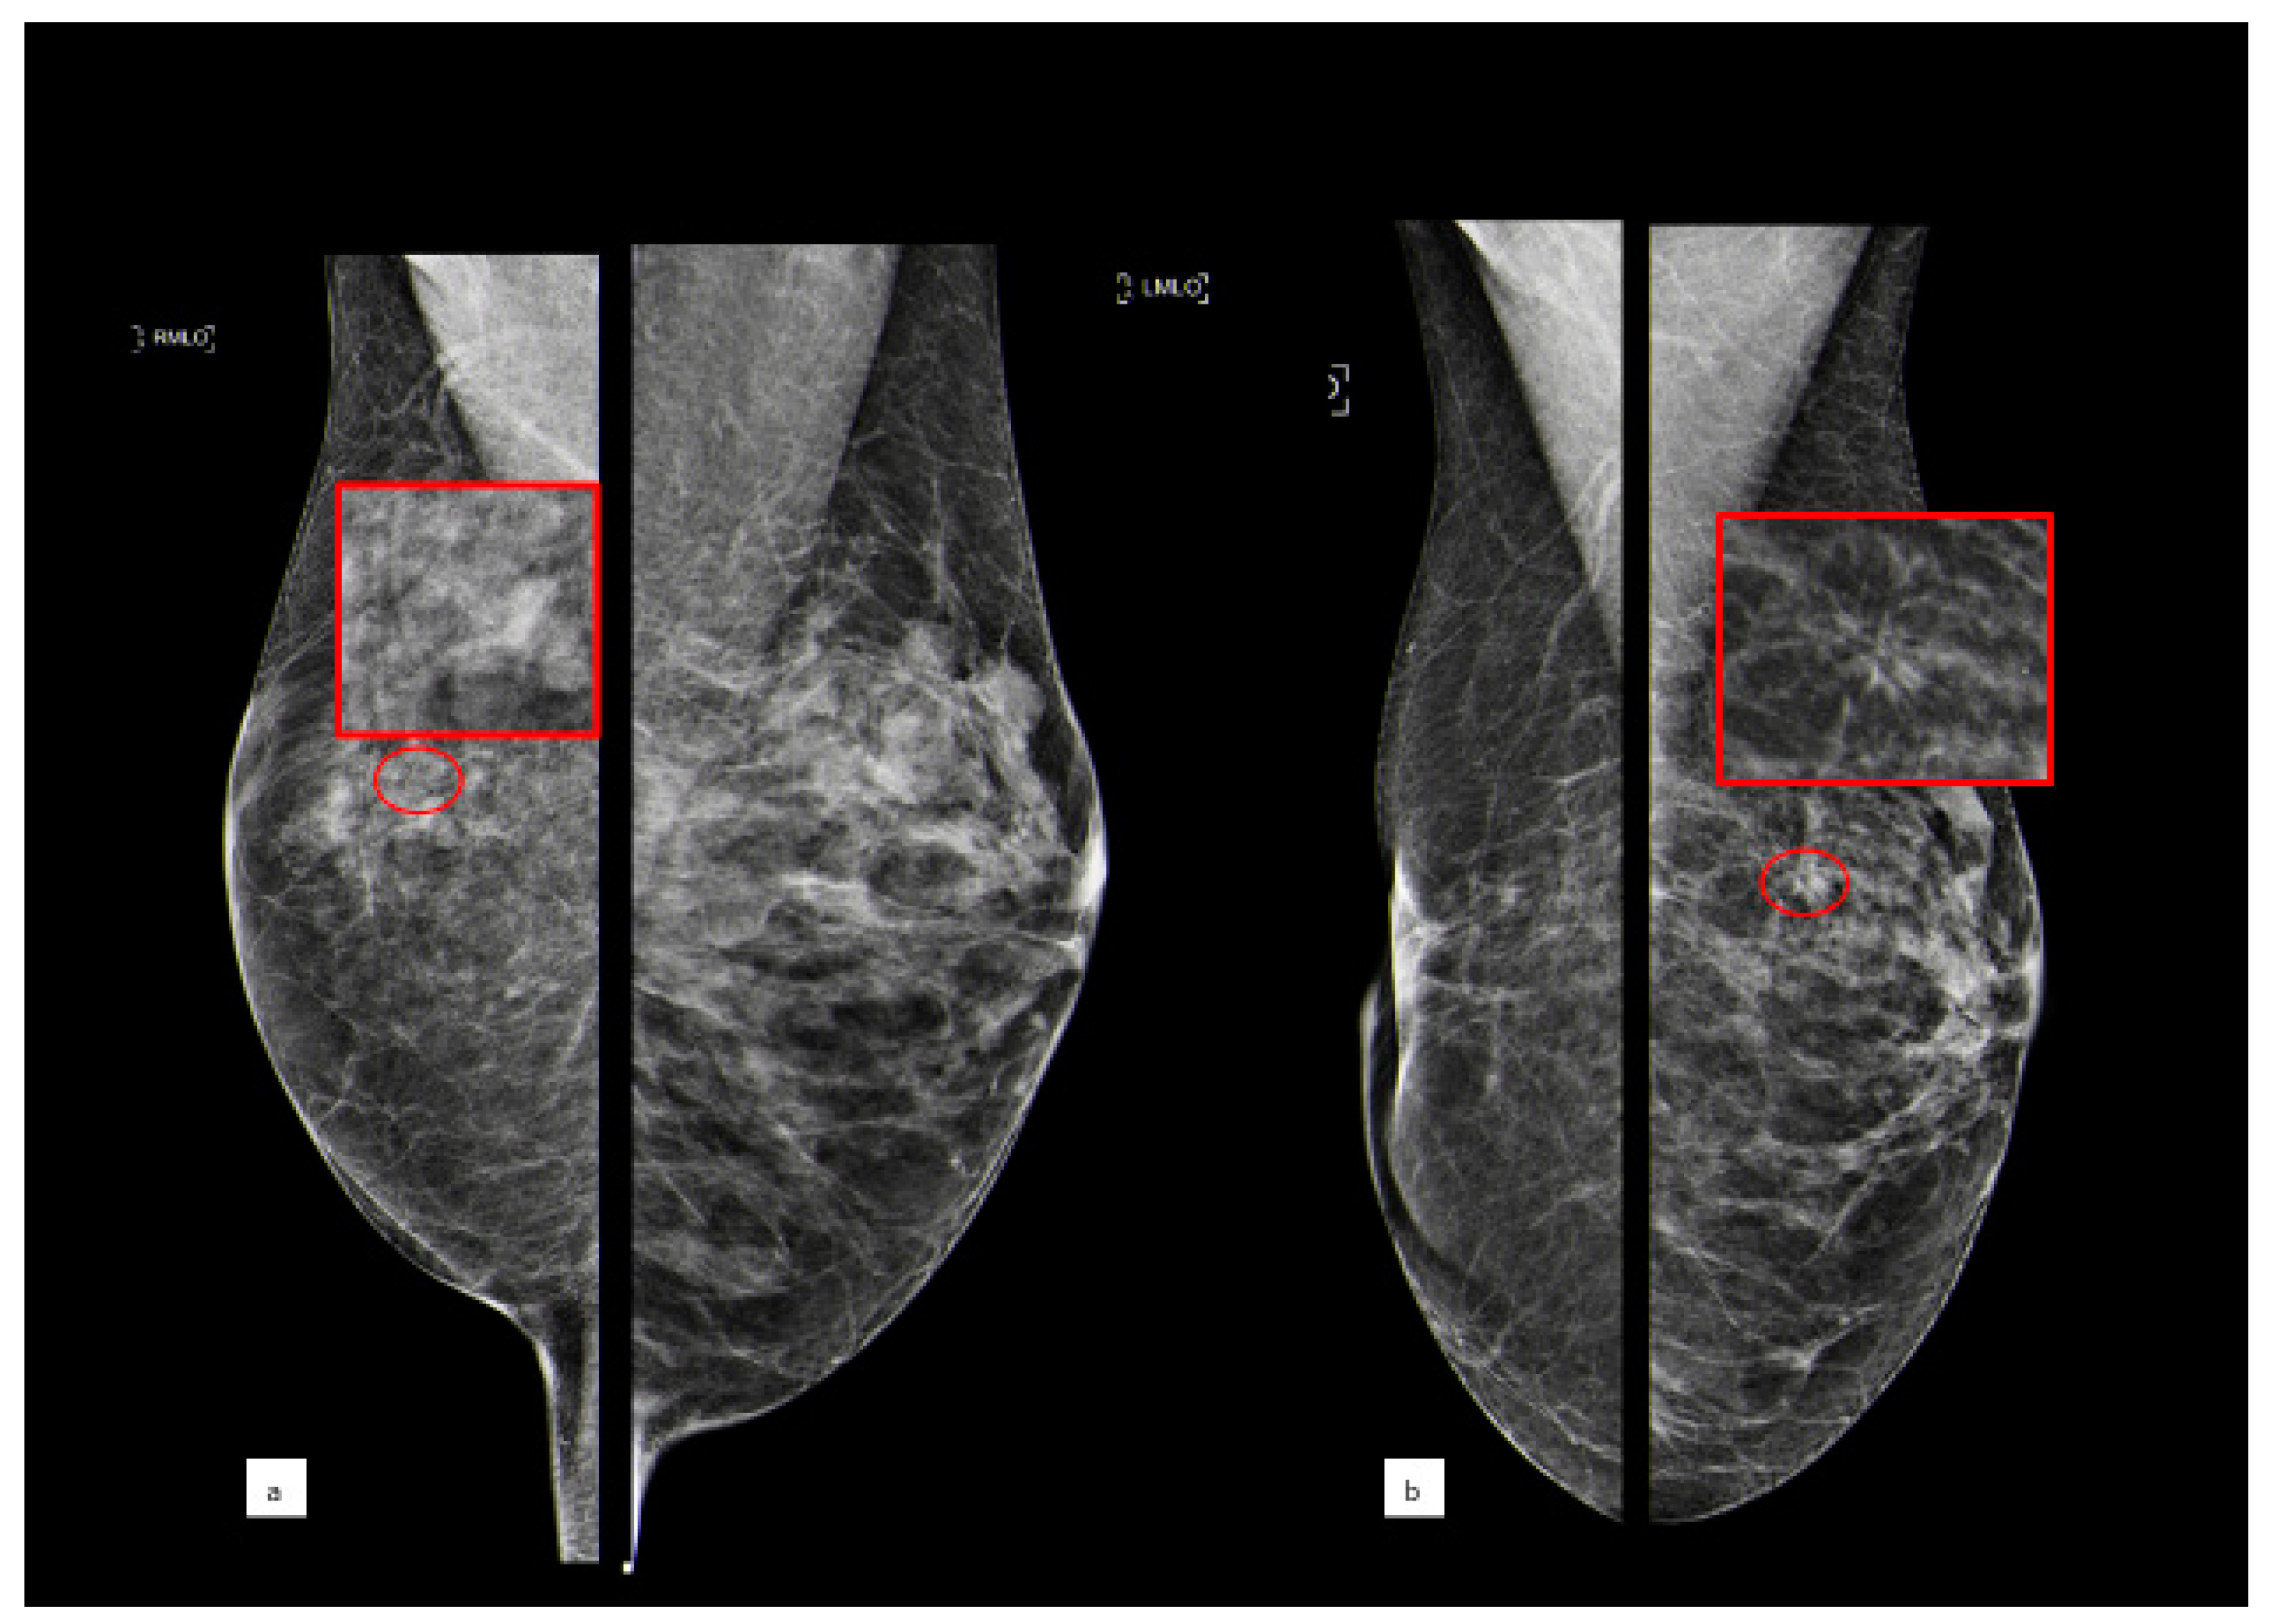

3.3.1. Flat Epithelial Atypia

3.3.2. Atypical Ductal Hyperplasia

3.3.3. Lobular Intraepithelial Neoplasia

3.3.4. Atypical Papillary Lesion

3.3.5. Phyllodes Tumors

3.3.6. Radial Scar